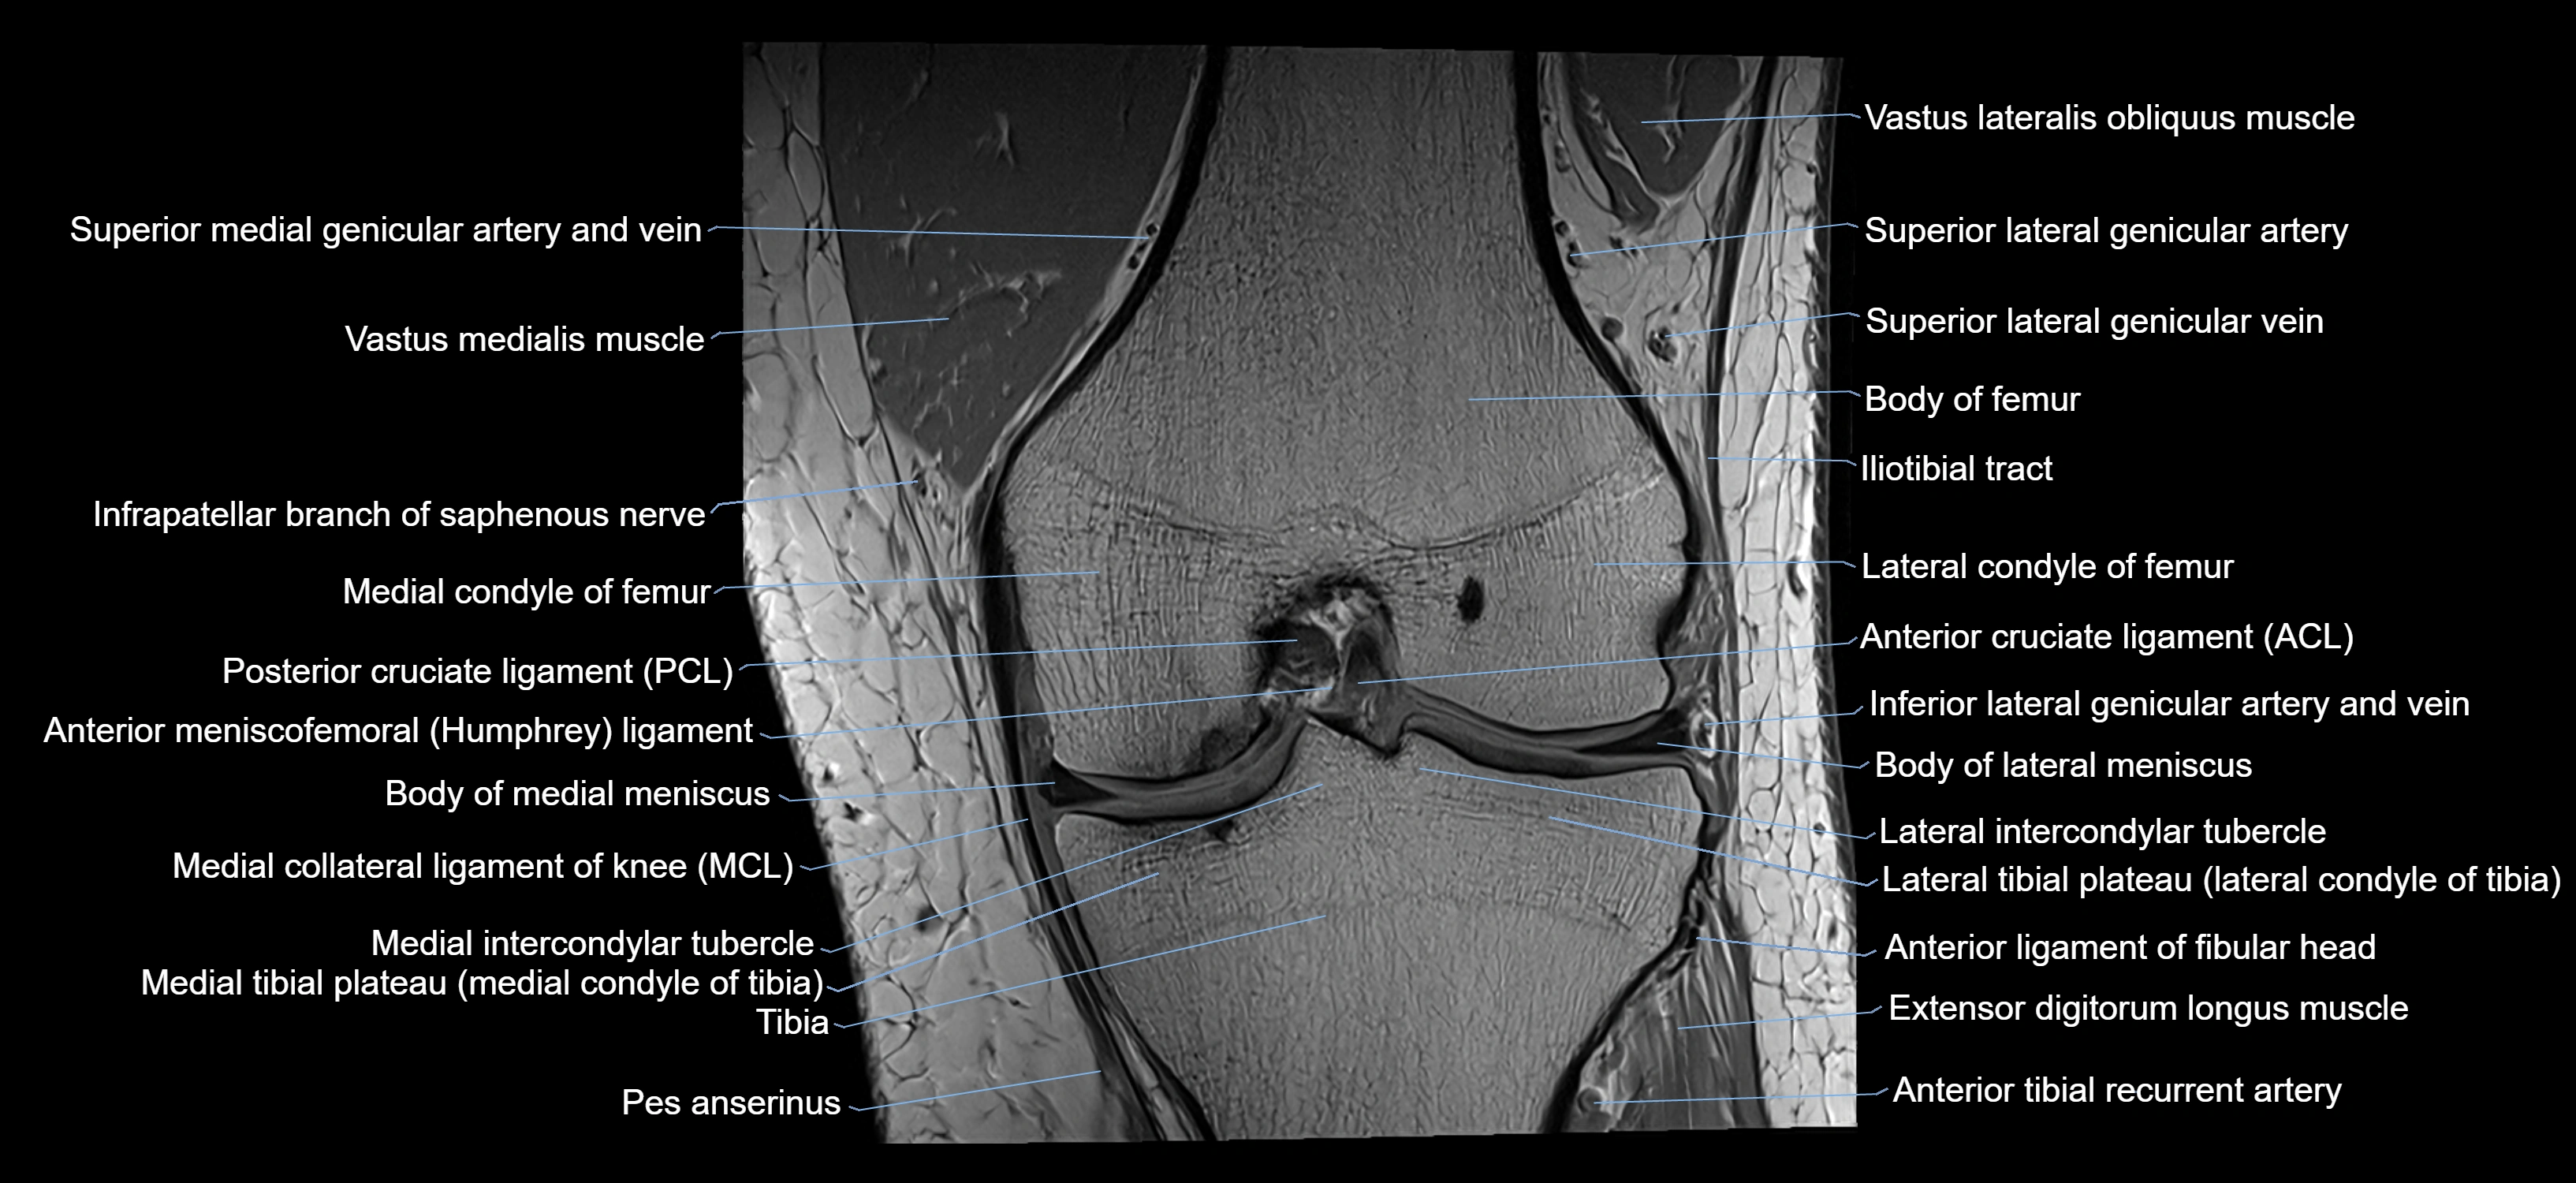

- Anterior cruciate ligament

- Anterior ligament of fibular head

- Anterior meniscofemoral ligament

- Body of lateral meniscus

- Body of medial meniscus

- Extensor digitorum longus muscle

- Gerdy’s tubercle

- Head of fibula

- Infrapatellar branch of saphenous nerve

- Lateral condyle of femur

- Lateral condyle of tibia

- Lateral intercondylar tubercle

- Lateral tibial plateau

- Medial collateral ligament

- Medial condyle of femur

- Medial condyle of tibia

- Medial intercondylar tubercle

- Medial tibial plateau

- Posterior cruciate ligament

- Superior lateral genicular artery

- Superior lateral genicular vein

- Superior medial genicular artery

- Tibia

- Tibialis anterior muscle

- Vastus Lateralis Obliquus Muscle

- Vastus lateralis muscle

- Vastus medialis muscle